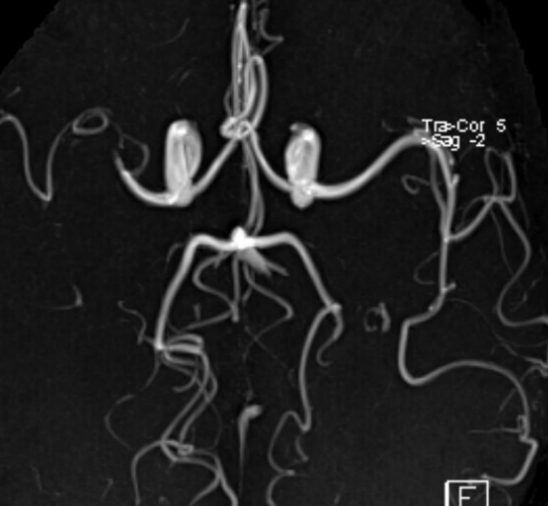

==> Rt M1 stenosis

TCD에서 우측의 MCA PV비가  좌측의 40%

RACA를 통한 측부순환 발달해 있음.

양측 경동맥에 죽상반이나 협착 없고, IMT가 1.2 mm 이하로 모두 정상.

O) MRI 에서 우측 BG에 쐐기모양의 old infarction 병변 보임. CTA에서 Rt M1 보다 원위부 혈관이 보이지 않음

진찰상 이상이 없으며, 본원 경두개 도플러 검사에서 Severe stenosis at the right proximal M1 로 나타났으며, Rt MCA의 혈류가 감소하여 있었으나, 유지되어 있고,

동측의 Common carotid A 압박시에 혈류감소가 없기 때문에 good collateral through AcomA 으로 생각됩니다.